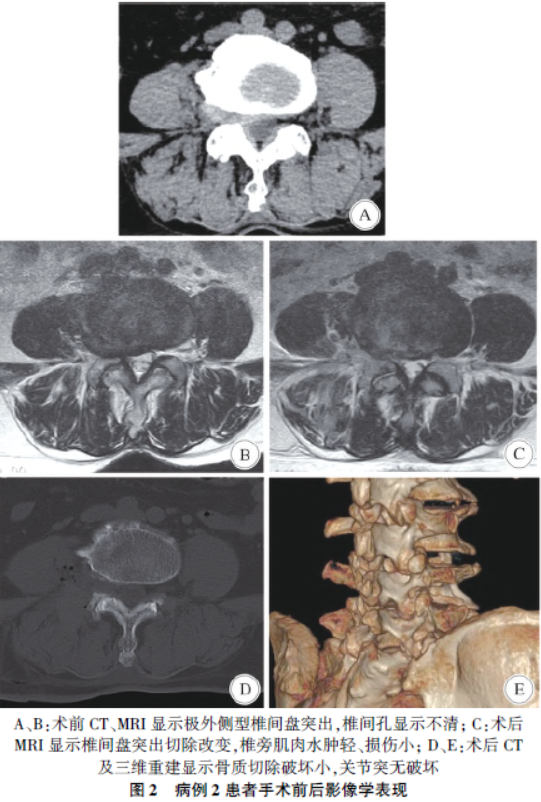

( magnetic resonance imaging,MRI)检查均提示L4/5 椎间孔及(或)外侧存在软组织影,神经根结构及周围脂肪间隙显示不清,均未见明显骨质增生及钙化压迫,其中病例1 椎间孔外侧软组织影一度误认为神经鞘瘤。见图1、图2。

1. 4 术后管理

患者术后第2 天下床活动,尽早鼓励患者行腰背肌锻炼。术后常规复查腰椎CT 三维重建了解关节突关节切除情况,复查腰椎MRI 了解椎间盘切除情况及神经根减压情况。术后3 ~4 日出院,2 周、1 个月、6 个月、1 年门诊或电话随访,采用VAS 评分评估术后症状缓解情况。